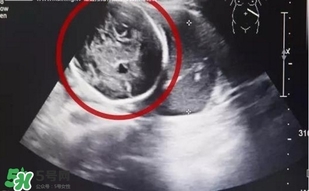

經(jīng)B超檢查,小芳竟然已經(jīng)懷孕了,而且胎兒已經(jīng)長到了6個多月!但是讓人震驚的是胎兒并沒有長在子宮里,而是長在了腹腔內(nèi)。醫(yī)生確診小芳為“腹腔妊娠”,也就是宮外孕的一種,這種發(fā)病率約為1:15000,母體死亡率約為5%,胎兒存活率僅為1%的罕見妊娠,竟然發(fā)生在了她的身上,而且小芳已經(jīng)出現(xiàn)肚子疼痛,情況十分緊急!